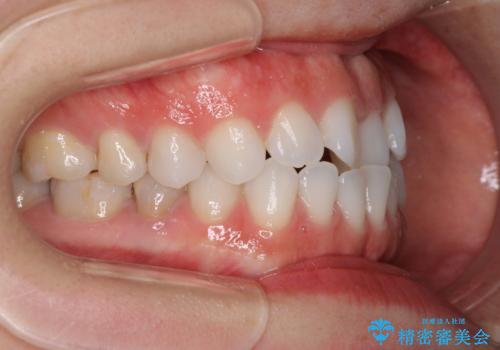

- 上下の前歯の反対咬合を気にして来院された患者様です。

インビザラインを用い、下顎はIPR(歯と歯の間を削る)と歯列全体を後方に移動させ、上顎は前歯を持ち上げることで、反対咬合を改善していくこととしました。

インビザラインによる反対咬合の改善は、上の歯が下の歯を乗り越えていく期間に咬み合わせが非常に不安定となり、治療が長期化することがあります。

こちらの患者様も、一時的に前歯でしか咬めない時期がありましたが、比較的早く咬み合わせが安定し、1年ほどで治療を終えることができました。